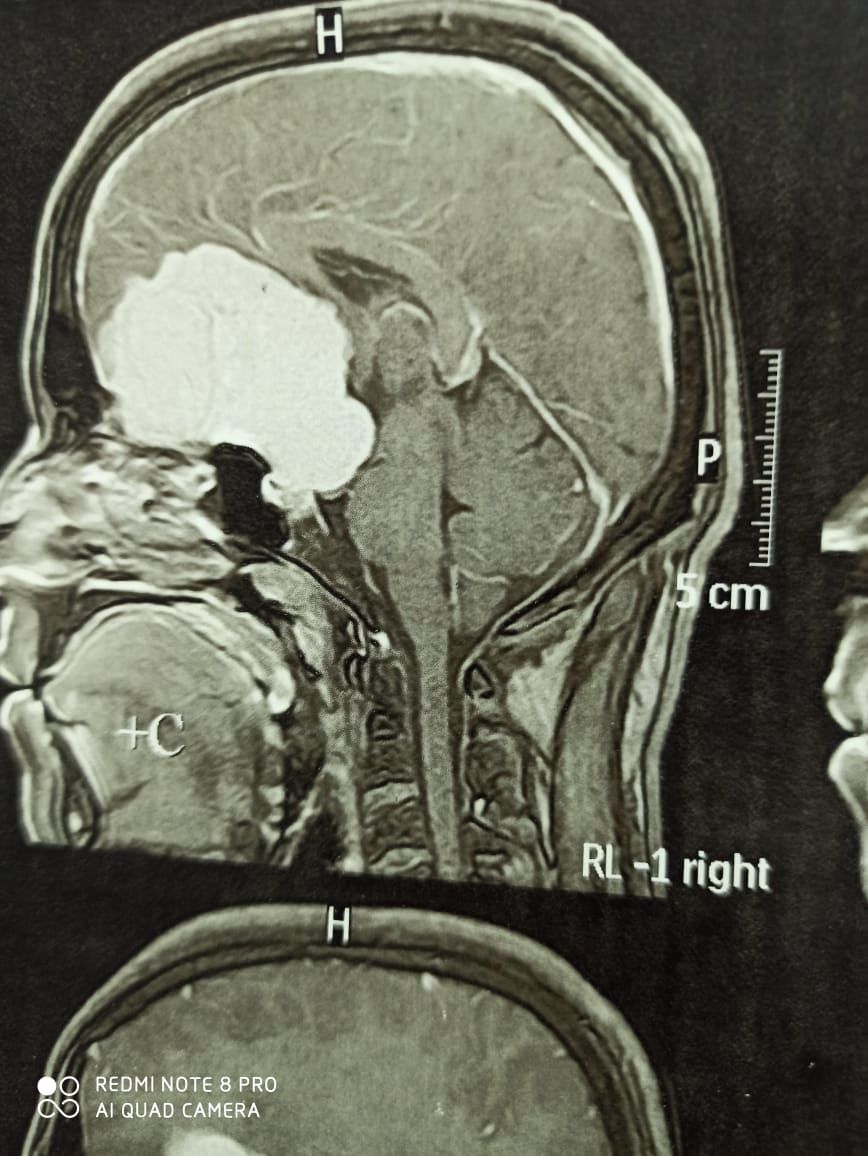

استئصال أكبر ورم في قاع الجمجمة يبلغ مساحته 132 سنتيمتر مربع ..

أخبار الجامعات.. حقق فريق طبي في قسم جراحة المخ والأعصاب، بالتعاون مع قسم التخدير في مستشفى سوهاج الجامعي التي تتبع جامعة سوهاج ، نجاح في إجراء عملية جراحية حساسة لاستئصال أكبر ورم في قاع الجمجمة يبلغ مساحته 132 سنتيمتر مربع.

حيث كان الشاب يعاني من مشاكل بالبصر وصداع مستمر وتغيرات في التصرف لمدة 3 سنوات، وتم إجراء العملية بنجاح بعد تدهور حالته الصحية.

وقد أكد الدكتور مجدي القاضي، عميد كلية الطب البشري ورئيس مجلس إدارة المستشفيات الجامعية في جامعة سوهاج، أن الشاب وصل إلى المستشفى في مرحلة متقدمة من فقدان البصر، لكنه تمكن من استعادته بعد العملية الجراحية الناجحة.